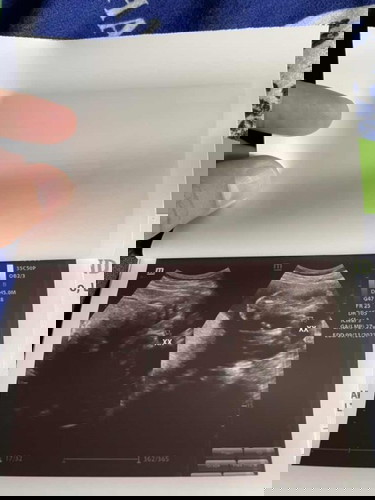

Gender ultrasound

Sure na po ba tong girl? Suhi at nakacross legs kasi siya, nahirapan yung mismong ob ko, pati yung ob sono na nagultrasound sakin ng cas. Hindi kasi sinabi nung ob sono kung 100%. Gusto ko po makasure, excited na ko mamili ng gamit, puro white palang kasi ang nabibili ko 😊 Thanks #firstbaby #going8months